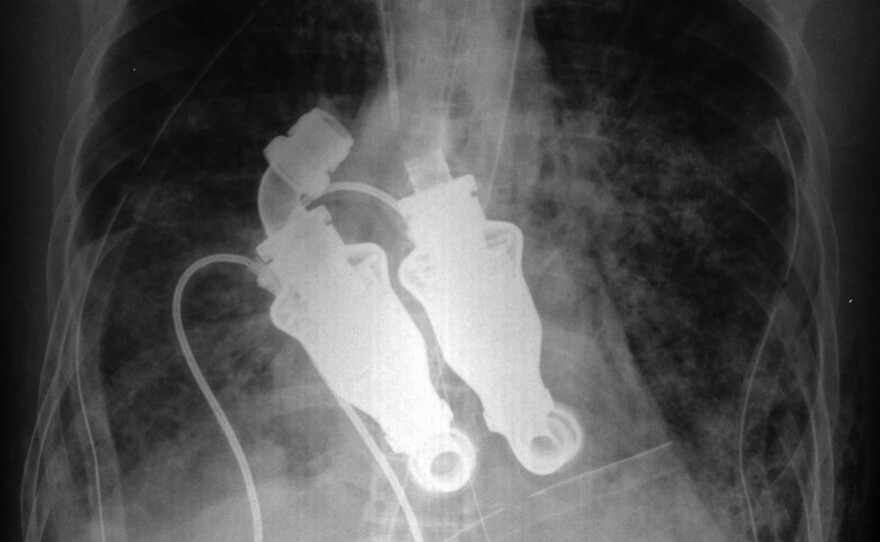

Cohn and Frazier did not start totally from scratch. They took two medical implants known as ventricular assist devices and hooked them together.

A ventricular assist device has a screwlike rotor of blades, which pushes the blood forward in a continuous flow.

Thousands of people have one of these implanted close to their hearts, including former Vice President Dick Cheney. By using two, the doctors replaced both the right and left ventricles — the entire heart.